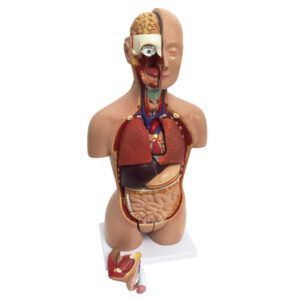

Tamanho natural do modelo de torso humano

Modelo de torso humano